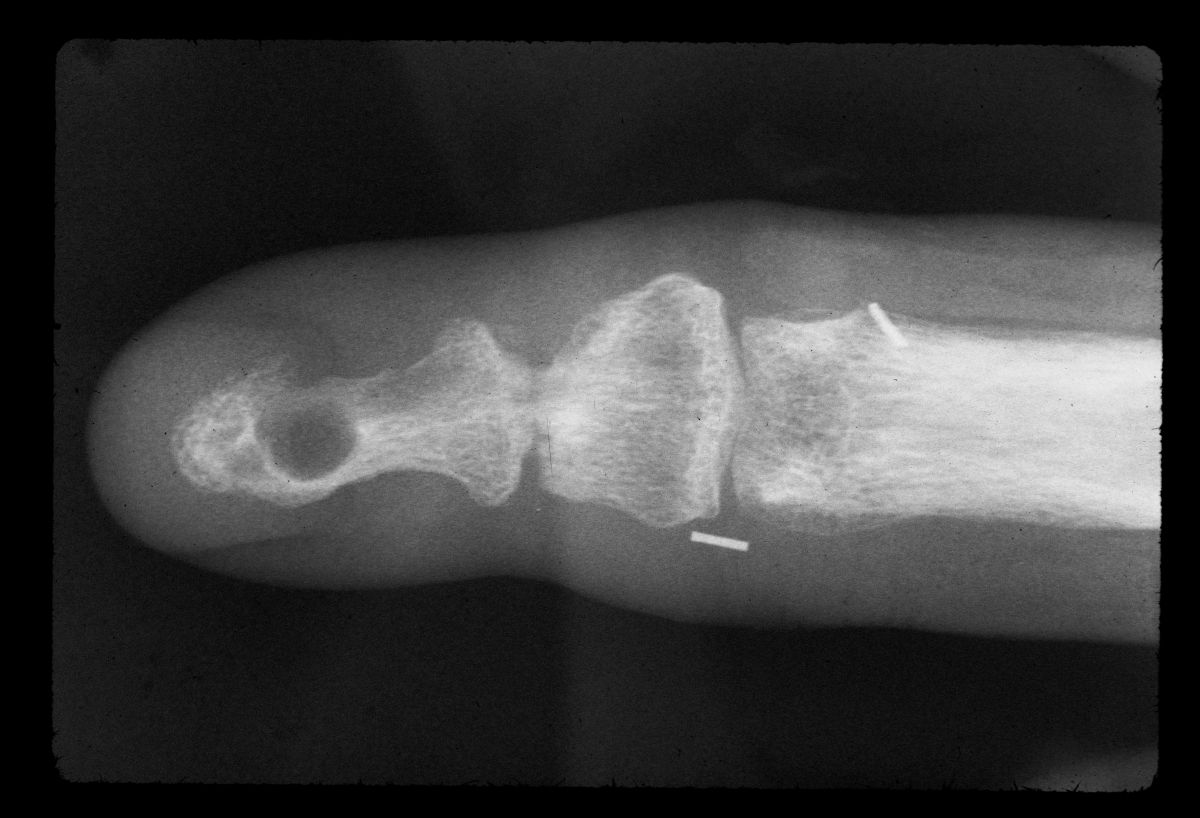

| Case 1. This patient presented with a progressive index finger nail deformity years after an open crush injury of that fingertip. |

| Xrays show loss of much of the distal half of the distal phalanx, with cortical disruption. |